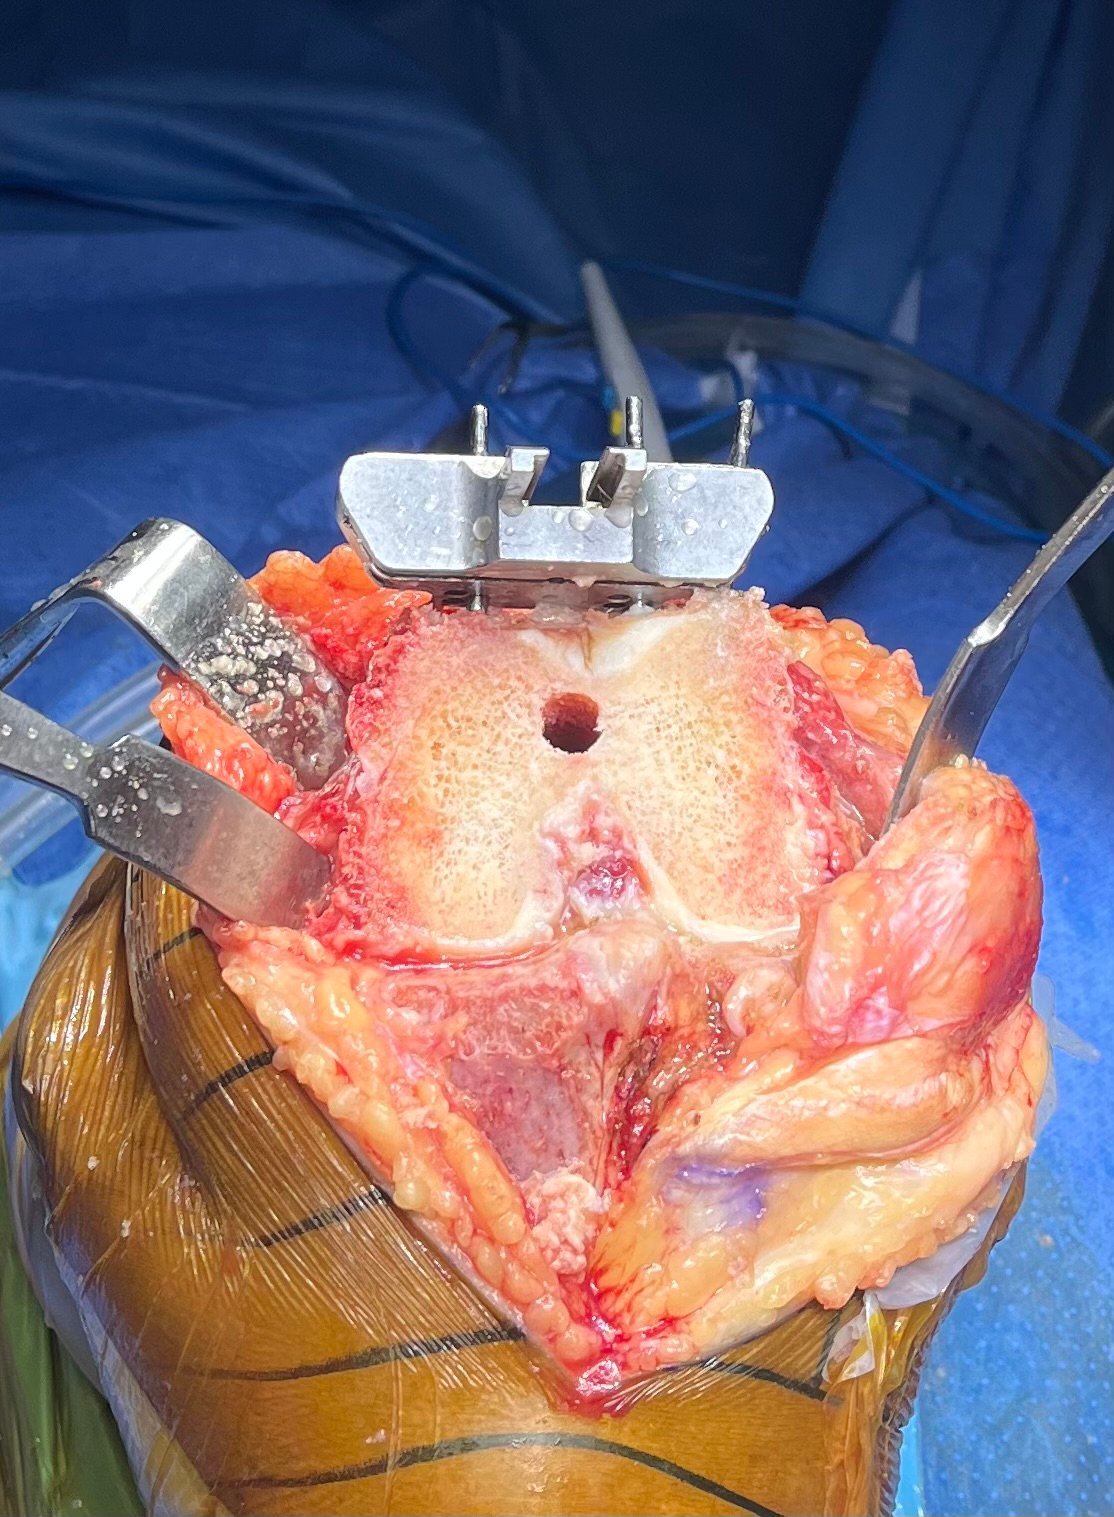

Rheumatoid Arthritis with Synovial Hypertrophy

Intra-Op (Photos)

Articular Cartilage Erosion

Femoral Entry